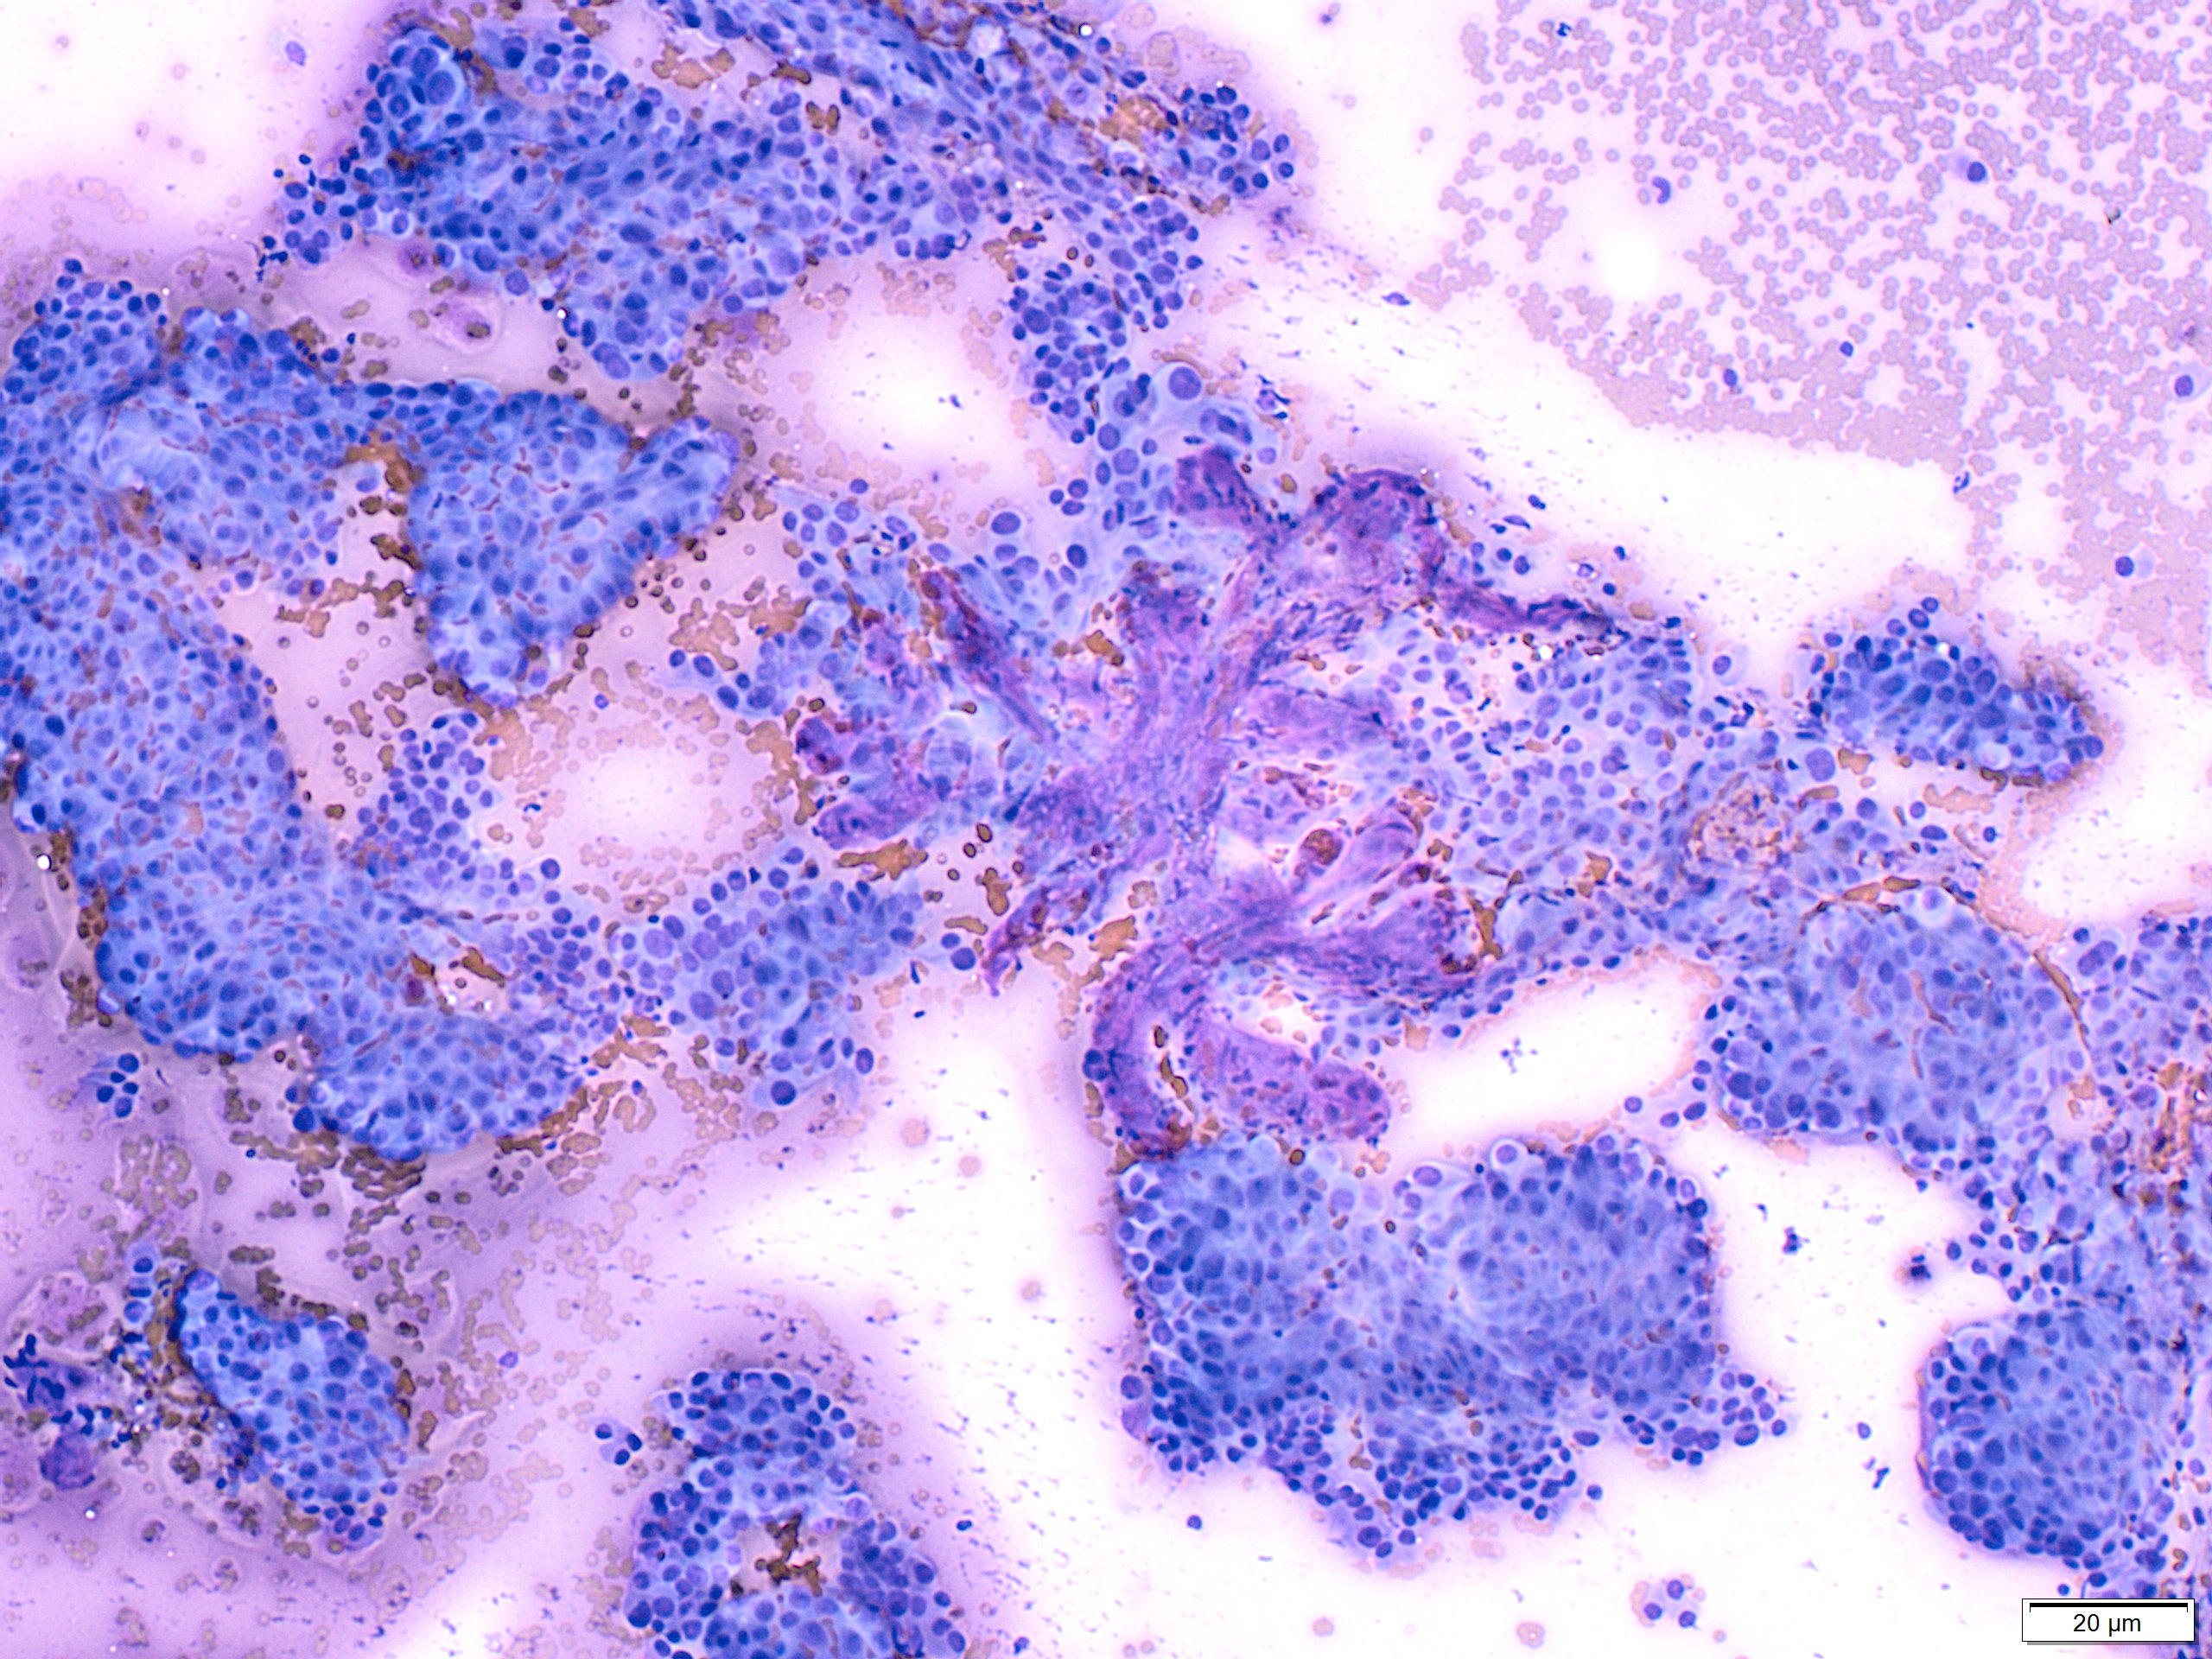

PTC is the most common thyroid malignancy in the United States. It can happen at any age with a female to male ratio of 3:1. The smear are usually cellular with sheets of follicular cells exhibiting nuclear overlapping and/or molding. The cytoplasm can be scant or abundant [squamoid, oncocytic (Picture #2) or vacuolated]. Intranuclear pseudoinclusions (black arrow) are specific to PTC and represent cytoplasmic invaginations. Other non-specific nuclear features include grooves (blue arrow) and nucleoli. Another highly specific feature is the presence of papillae with fibrovascular cores (Picture #3).